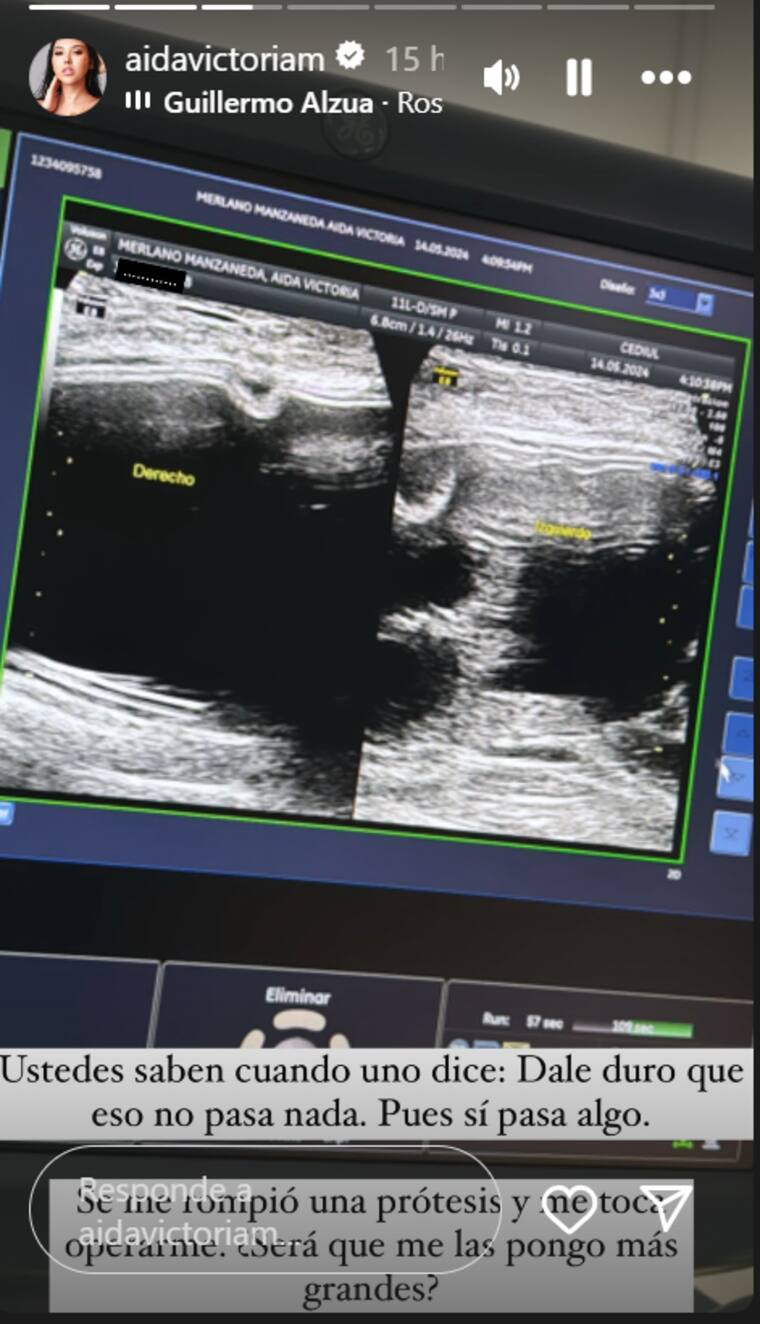

Sin embargo, la joven publicó en sus historias de Instagram una fotografía que preocupó a sus seguidores. “¿Ustedes saben cuando uno dice: ‘Dale duro que eso no pasa nada’?, pues sí pasa algo. Se me rompió una prótesis y me toca operarme. ¿Será que me las pongo más grandes?”, escribió Merlano.

No precisó qué fue lo que le pasó, pero no está asustada por la situación, sino que está pensando en hacer una pequeña modificación.

“Mis prótesis tenían garantía, así que no te preocupes, no te preocupes. Ahora lo que vamos a decidir es el tamaño”, dijo Aida.